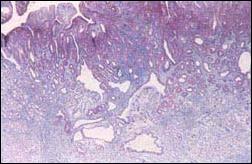

Consideramos interesante reproducir el estudio histológico de la clasificación de Elster del libro original a Seifert y Elster. (Fotos 9, 10, 11, 12 y 13)

FOTOGRAFÍAS ORIGINALES DE LA CLASIFICACION DE ELSTER

Foto 9.- Pólipo tipo 1 hiperplasia focal

Foto 10.- Pólipo tipo 2 hiperplasiogénico

Foto 11.- Pólipo 3 adenoma de bajo grado

Foto 12.- Pólipo categoría 4 lesión limite

Foto 13.- Tipo 5 cáncer temprano lla

Lo que es necesario señalar en esta clasificación, es describir la lesión límite de carácter protuido y las formas IIa y IIa + IIc como adenomas malignizados, ya que este autor señala como adenoma I y adenoma II a los tipos 3 y 4 de su clasificación.